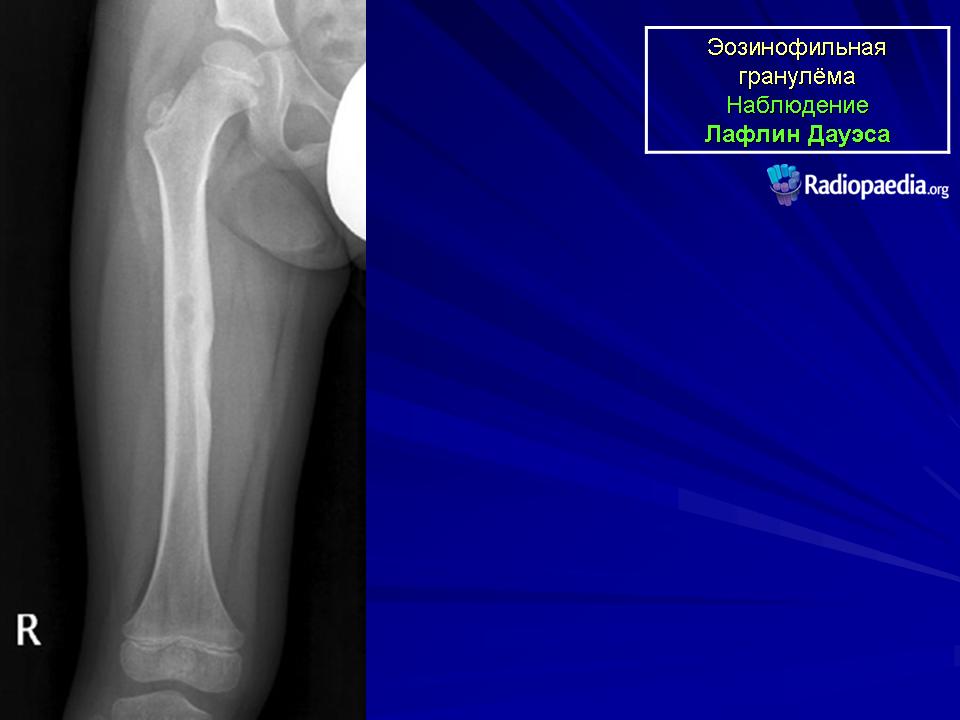

LCH. Девочка в возрасте 1 год 11 месяцев.

Литический очаг (стрелка) в диафизе б/берцовой кости, с узкой зоной «перехода».